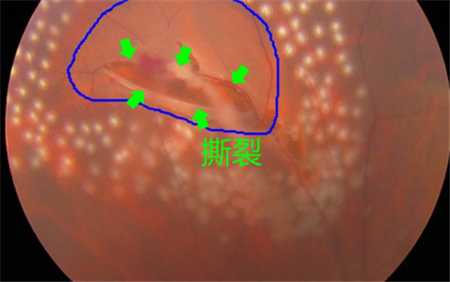

如果是一些嚴重眼疾如后玻璃體脫落、視網膜撕裂、糖尿眼或老年黃斑退化導致玻璃體出血、葡萄膜炎等導致的飛蚊癥,則屬于病理性飛蚊,也稱為惡性飛蚊。這些眼疾若未及時治療,嚴重情況下可導致眼睛失明。

例如,對于視網膜撕裂引起的飛蚊癥,就需要對視網膜撕裂進行治療,通過激光將裂孔周圍進行燒焊凝固,以避免積水擴散造成嚴重的視網膜脫落;若飛蚊癥是由葡萄膜炎所致,就需要及時治療葡萄膜炎;對于糖尿眼導致的玻璃體出血,則需要通過激光治療以減少或避免增生血管的產生。